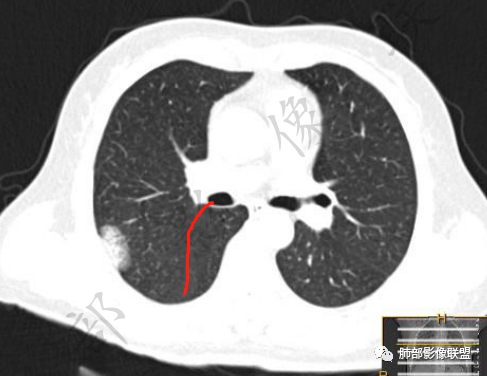

2、影像所见:右肺上叶后段混合密度磨玻璃影mGGN,整体膨隆为主,局部收缩,局部边缘可疑月牙铲。周围磨玻璃影边界清楚,边缘分叶,细细观察这种清楚的弧形边界,与小叶间隔是否高度契合?!

结节内血管影增粗。病灶附近血管纠集,临近胸膜轻度增厚,叶间胸膜轻度牵拉移位。综合考虑恶性,腺癌可能。(局部胸膜增厚,考虑为肿块局部牵拉为主造成的)。